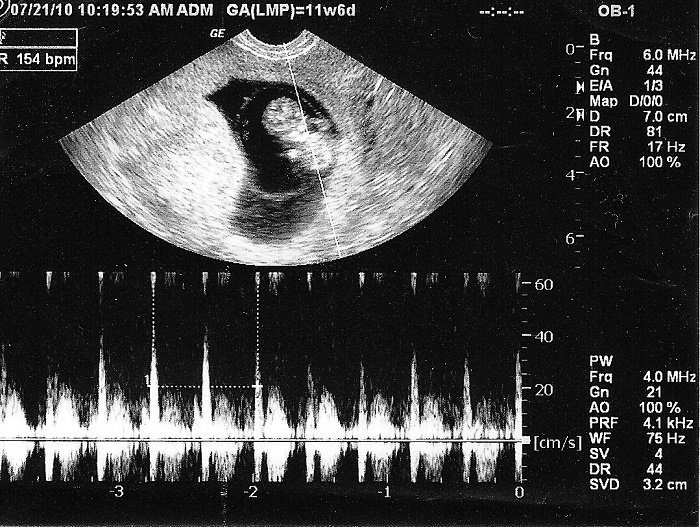

6. Nhịp Tim Thai Bất Thường

Nhịp tim bình thường: 120-160 lần/phút.

Bất thường: Nhịp tim nhanh hoặc chậm có thể báo hiệu thai nhi bị suy thai, thiếu oxy.

Cách theo dõi: Sử dụng máy nghe tim thai tại nhà hoặc siêu âm Doppler.